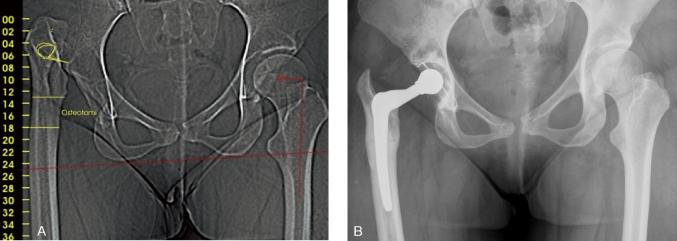

The prostheses are produced by CAD-CAM technique. The design of the stem is based on CT information, and the neck design is based on the surgeon's planning of the center of rotation, femoral head offset, and leg length correction. The first-generation stem produced before 2001 had a proximal HA coating and a sand-blasted distal part that was down-scaled to avoid contact with compact bone. The second-generation stem had a porous coating beneath the HA layer and the distal part of the stem was polished. The implant was used in 762 hips (614 patients) from 1995 until 2009. 191 of these hips were followed for 7 years and 83 others were followed for 10 years, and these hips are included in the present study. Mean age at surgery was 48 (20-65) years. Congenital dysplasia of the hip was the reason for osteoarthritis in 46% and 57% of the hips in respective groups. Merle d'Aubigné score was recorded in 152 and 75 hips in the two groups. Prostheses followed for 10 years, and almost all in the 7-year group, were first-generation stems.

假体采用 CAD-CAM 技术制造。假体柄的设计基于 CT 信息,颈的设计基于术者对旋转中心、股骨头偏心距和下肢长度校正的规划。第一代假体在 2001 年之前生产,具有近端 HA 涂层和喷砂处理的远端部分,其缩径设计避免与密质骨接触。第二代假体具有 HA 层下的多孔涂层,假体的远端部分经过抛光。1995 年至 2009 年期间,该假体应用于 762 髋(614 例患者)。其中 191 髋随访 7 年,83 髋随访 10 年,这些髋关节均纳入本研究。手术时的平均年龄为 48 岁(20-65 岁)。髋关节先天性发育不良是导致 46%和 57%髋关节发生骨关节炎的原因。两组中分别有 152 髋和 75 髋记录了 Merle d'Aubigné 评分。随访 10 年的几乎均为第一代假体,而随访 7 年的假体中第一代和第二代假体各占一半。以任何原因翻修为终点,7 年和 10 年的累计翻修率分别为 1.1%和 2.4%。7 年和 10 年时临床结果相似,Merle d'Aubigné 评分为 17 分。191 髋中有 2 髋术中发生大转子骨折(1.0%),均经钢丝环扎固定后愈合。随访 7 年时,2 髋发生假体周围骨折,均需翻修假体。1 髋在随访 7-10 年时发生 1 处骨折,经骨愈合治疗后成功。脱位率分别为 1.6%和 2.4%。随访时无影像学松动。